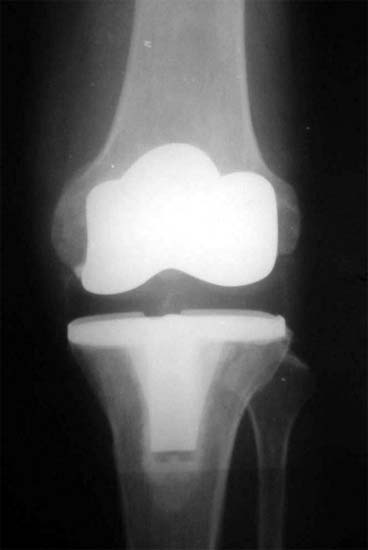

术后X线片,假体用骨水泥固定显示膝内翻被纠正

70岁,软骨破坏,严重双膝内翻畸形

双膝关节X线片显示关节软骨破坏,间隙消失,膝内翻